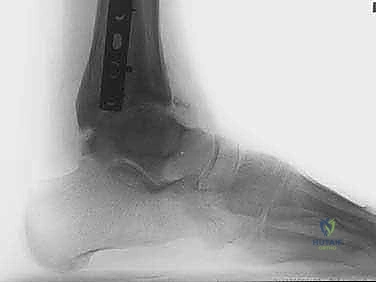

- الأشعة السينية (X-rays) مع الوقوف: لتقييم المسافة المتبقية من المفصل وتحديد درجة الخشونة ومحور الساق.

- الأشعة المقطعية (CT Scan): للحصول على صورة ثلاثية الأبعاد للعظام، واكتشاف أي تكيسات عظمية (Bone cysts) أو نتوءات عظمية (Osteophytes).

- الرنين المغناطيسي (MRI): لتقييم حالة الغضروف المتبقي، والأربطة، والأنسجة الرخوة، والوذمة العظمية (Bone marrow edema).

- زيادة مساحة المفصل: تظهر الأشعة السينية بوضوح اتساع المسافة بين عظام الكاحل، وهو دليل قاطع على تجدد النسيج الغضروفي.